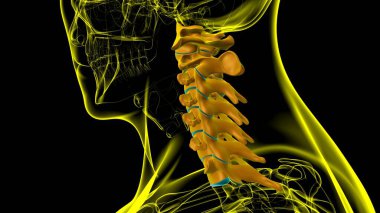

İnsan İskeleti Omurgası Servikal Omurga Anatomisi 3D İllüstrasyon

İnsanTıbbiparmakBoyunomurgaKalçaRADIUSsakralGöğüs kemiğiskapulaLeğen kemiğitorasikçene kemiğiparietallombersakrumTibiaUyluk kemiğiKöprücük kemiğisokumupazı kemiğidirsek kemiğioksipitaldiz kapağıkemikler3d oluşturmaGöğüs kafesiüst ekstremiteOmurga SütunuAyak bileği Ağrısıbel kemiğiayak kemikleriiskelet anatomisidiz eklem ağrısıservikal bölgeclavicle bonewrist carpalscervical vertebrae anatomyBenzer İçerikler